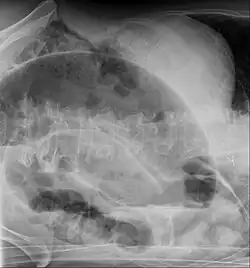

An x-ray of a person with a small bowel volvulus.